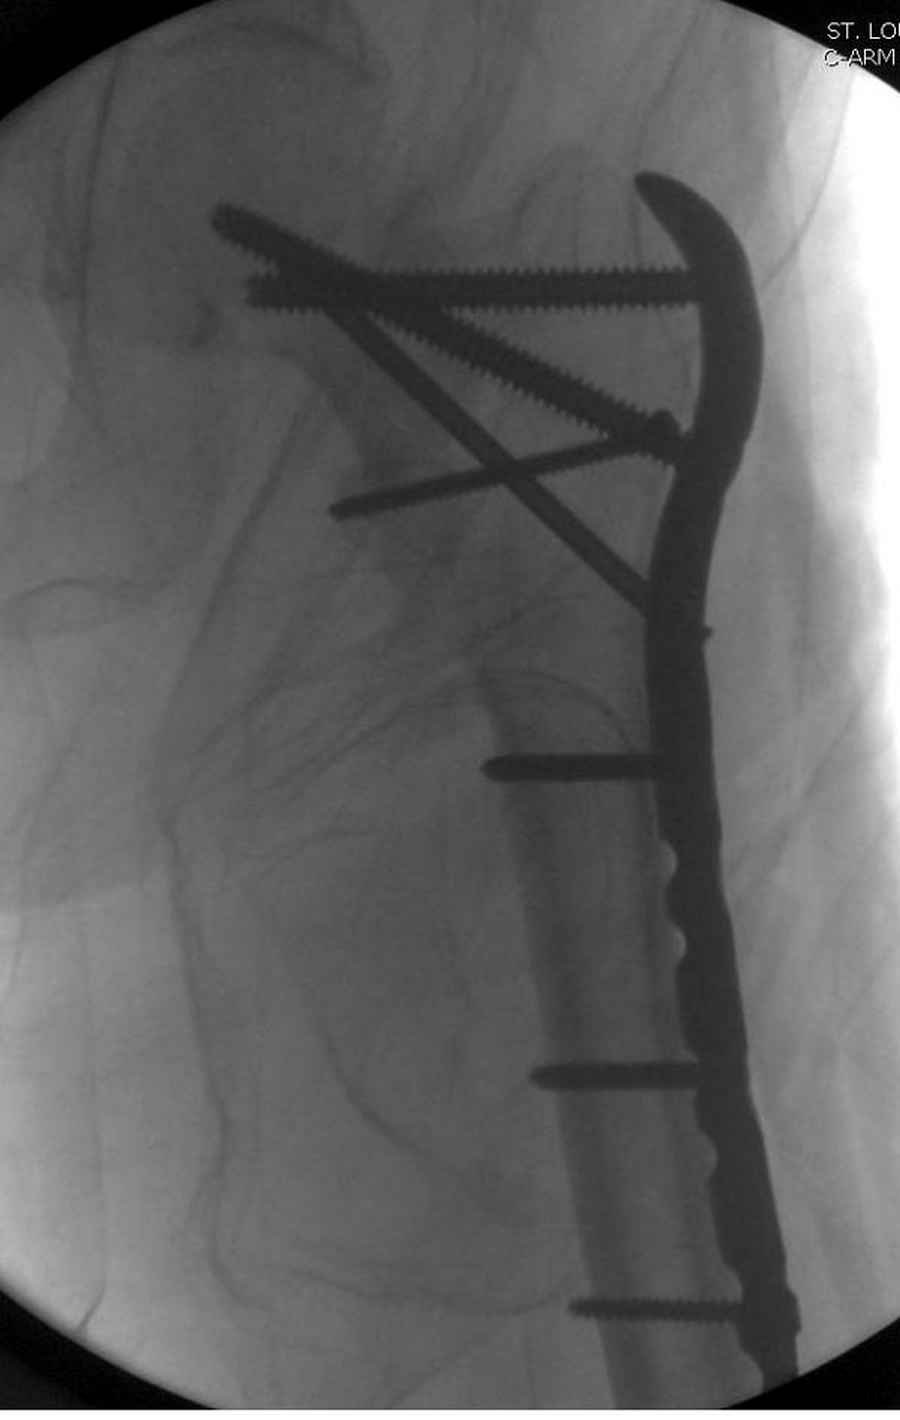

Из фиксаторов, мы бы применили цефаломедуллярные, потому что они "по закону моментов" из-за короткого рычага от центра головки к диафизу и по принципу "головка диафиз" механически лучше выдерживают нагрузки, чем пластины.

Но современные пластины с угловой стабильностью не отстают от медуллярных конструкций. Межфрагментарные шурупы и имплант как нейтрализирующее создаст адекватную фиксацию.

Здесь пара случаев фиксации похожих переломов:

первый высокоэнергетическая травма 36 лет

судя по картинкам с ЭОПа явно использовались приемы непрямой репозиции под его контролем, а так же интраоперационный ЭОП-контроль положения винтов, без такого контроля операция может ухудшить ситуацию (опять же учтите сроки) т.к. результат буде зависеть в большей степени от искусства хирурга, а не от технологии